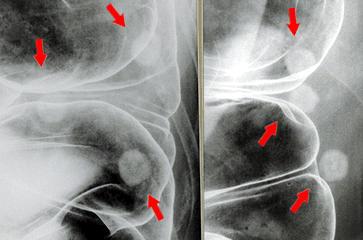

疾病(病理主体)的分类肿瘤样病变/其他

部位(按器官分)大肠/降结肠

检查方法X线

肿瘤最大直径10~14

多发性肿瘤(同一器官)有(同时性)